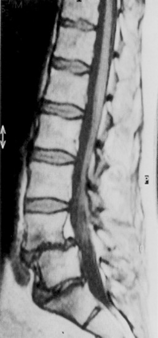

MRI lumbar spine (sagittal plane)

There is anterolisthesis of the L4 vertebral body. pondylolisthesis